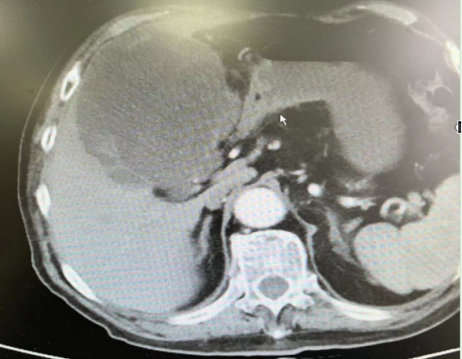

辅助检查:BNP正常。2022-10-15 腹部脏器(常规):肝内混合回声团:肝脓肿?请结合临床。2022-10-16 上腹部CT(平扫,增强扫描):肝右叶团块影,考虑感染性病变(大小约12.0*10.5*9.6cm)。

20221026日复查腹部CT提示:肝右叶团块影,考虑感染性病变,目前病变略较前增大(大小约12.0*11.5*10.2cm)。